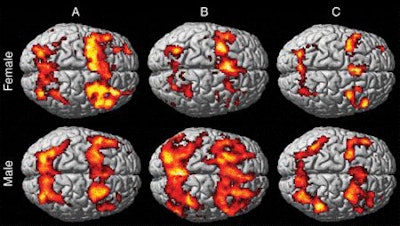

Initial fMRI scans of the MTBI patients showed increased activation in working memory brain circuits in the men and decreased activation in the women, compared with the controls.

Most significantly, at the six-week follow-up fMRI scan, female patients with MTBI showed persistent hypoactivation, which suggests ongoing working memory problems. In contrast, the hyperactivation in the male MTBI patients had regressed and they had returned to a more normal level of activation, similar to what was seen in the control subjects.